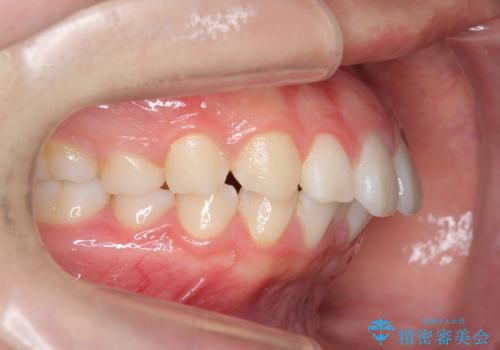

- 前歯の目立つねじれを矯正治療で治したい、と来院されました。

マウスピース矯正を始める前に、ねじれを取るのが短期間で済む部分ワイヤー小矯正を行うことで、全体的な治療期間を短くする治療計画を実行していきます。

前歯のねじれはマウスピース矯正の苦手な動きになり、治療期間が長くなる原因になりやすいです。